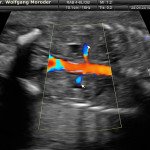

A fianco alla più tradizionale ecografia eseguita per via transaddominale, risulta particolarmente utile nell’esame ecografico ostetrico e ginecologico la via di accesso transvaginale.

Con questa metodica, utilizzando delle sonde ecografiche appositamente predisposte (per forma e dimensione, e per frequenza di emissione degli ultrasuoni) è possibile controllare la gravidanza nel primo trimestre con una qualità e definizione d’ immagine nettamente superiori a quanto possibile per via transaddominale.

Per eseguire l’ecografia transvaginale non è richiesta la vescica piena, diversamente rispetto a quanto richiesto per l’ecografia transaddominale. L’approccio transvaginale consente di aggirare l’ostacolo dovuto ad un aumentato spessore della parete addominale (obesità). In questi casi infatti la qualità d’ immagine in caso di ecografia transaddominale viene fortemente penalizzata dall’eccessivo spessore del pannicolo adiposo addominale.

Con l’ecografia transvaginale è possibile vedere dopo circa 3 settimane dal concepimento la camera gestazionale nella cavità uterina. Successivamente è possibile visualizzare l’embrione (3-5 mm.) a circa 6 settimane dall’ultima mestruazione (4 settimane dal concepimento) ed a questo periodo è già visibile l’attività cardiaca fetale Anche i primi dettagli sulla morfologia fetale (polo cefalico, abbozzi degli arti) sono visualizzabili più precocemente con l’ecografia transvaginale, risultando essi visibili intorno a 8-9 settimane.

Con l’ecografia dei primi mesi di gravidanza, si può anche valutare la normalità dell’utero (eventuale presenza di fibromi già preesistenti alla gravidanza) e delle ovaie.

Con il finire del primo trimestre per il controllo ecografico di routine della gravidanza la via transvaginale viene poi sostituita dalla via transaddominale.

Successivamente può risultare utile il ricorso all’ ecografia transvaginale nei casi in cui si sospettino delle modificazioni precoci (raccorciamento) del collo dell’utero, come potrebbe verificarsi nei casi di minaccia d’ aborto o di parto pretermine.

In questi casi infatti è possibile con l’ ecografia misurare con precisione la lunghezza del collo uterino. In questi casi inoltre l’ ecografia può anche evidenziare un’ iniziale dilatazione dell’ orifizio uterino interno. Tali modificazioni del collo dell’ utero, valutabili con accuratezza solo con l’ ecografia transvaginale, hanno una grande importanza nel considerare un eventuale rischio di parto pre-termine.